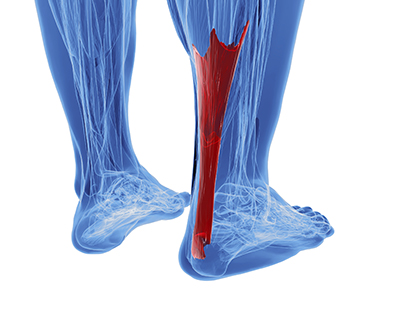

The Achilles tendon is the strongest tendon in the human body. Its purpose is to connect the lower leg muscles and calf to the heel of the foot. This tendon is responsible for facilitating all types of movement, like walking and running. This tendon provides an enormous amount of mobility for the body. Any injuries inflicted to this tissue should be immediately brought up with a physician to prevent further damage.

The Achilles tendon is the strongest tendon in the human body. Its purpose is to connect the lower leg muscles and calf to the heel of the foot. This tendon is responsible for facilitating all types of movement, like walking and running. This tendon provides an enormous amount of mobility for the body. Any injuries inflicted to this tissue should be immediately brought up with a physician to prevent further damage.

The most common injuries that can trouble the Achilles tendon are tendon ruptures and Achilles tendinitis. Achilles tendinitis is the milder of the two injuries. It can be recognized by the following symptoms: inflammation, dull to severe pain, an increased flow of blood to the tendon, thickening of the tendon, and slower movement time. Tendinitis can be treated via several methods and is often diagnosed by an MRI.

An Achilles tendon rupture is trickier to heal, and is by far the most painful injury. It is caused by the tendon ripping or completely snapping. The results are immediate and absolutely devastating, and will render the patient immobile. If a rupture or tear occurs, operative and non-operative methods are available. Once the treatment begins, depending on the severity of the injury, recovery time for these types of issues can take up to a year.